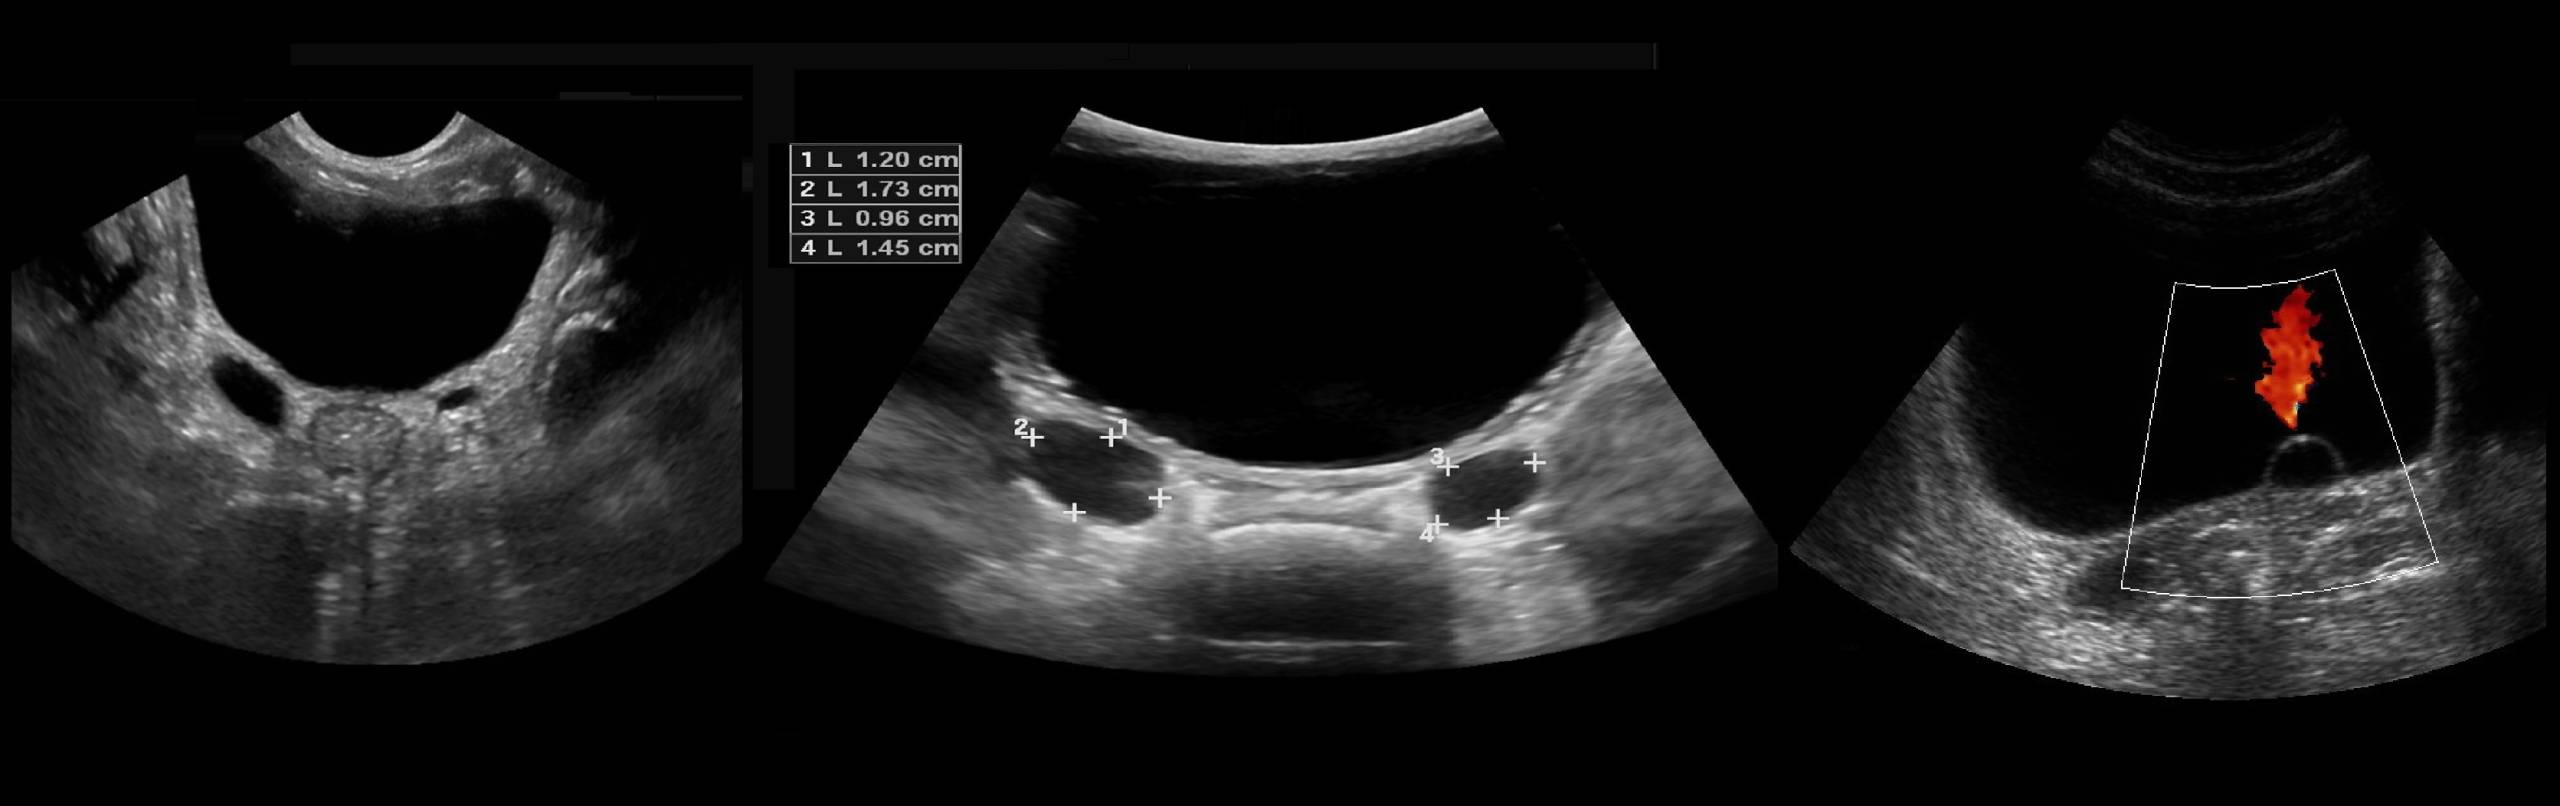

Мочеточниковые выбросы на УЗИ

Существует шесть различных типов мочеточниковых выбросов, которые характерны для разнличной физиологической и патологической активности сфинктеров пузырно-мочеточникового соединения. Среди них двухфазные, трехфазные и многофазные кривые относят к зрелой активности сфинктера, в то время как монофазная струя классифицируется как незрелая струя, характерна для младших детей.

Мочеточниковые отверстия не видны, но их расположение можно угадать по мочеточниковым выбросам при ЦДК. Иногда можно заметить расширение мочеточника до 3-4 мм при прохождении порции мочи. Мочеточниковые струи должны пересекаться строго по средней линии мочевого пузыря. Это подтверждает двустороннюю почечную функцию и исключает полную мочеточниковую обструкцию, но не частичную. Для «зрелого» пузырномочеточникового соединения характерна двух- или трехволновая кривая.

Рисунок

. Одно-, двух-, трехволновая кривая мочеточникового выброса.